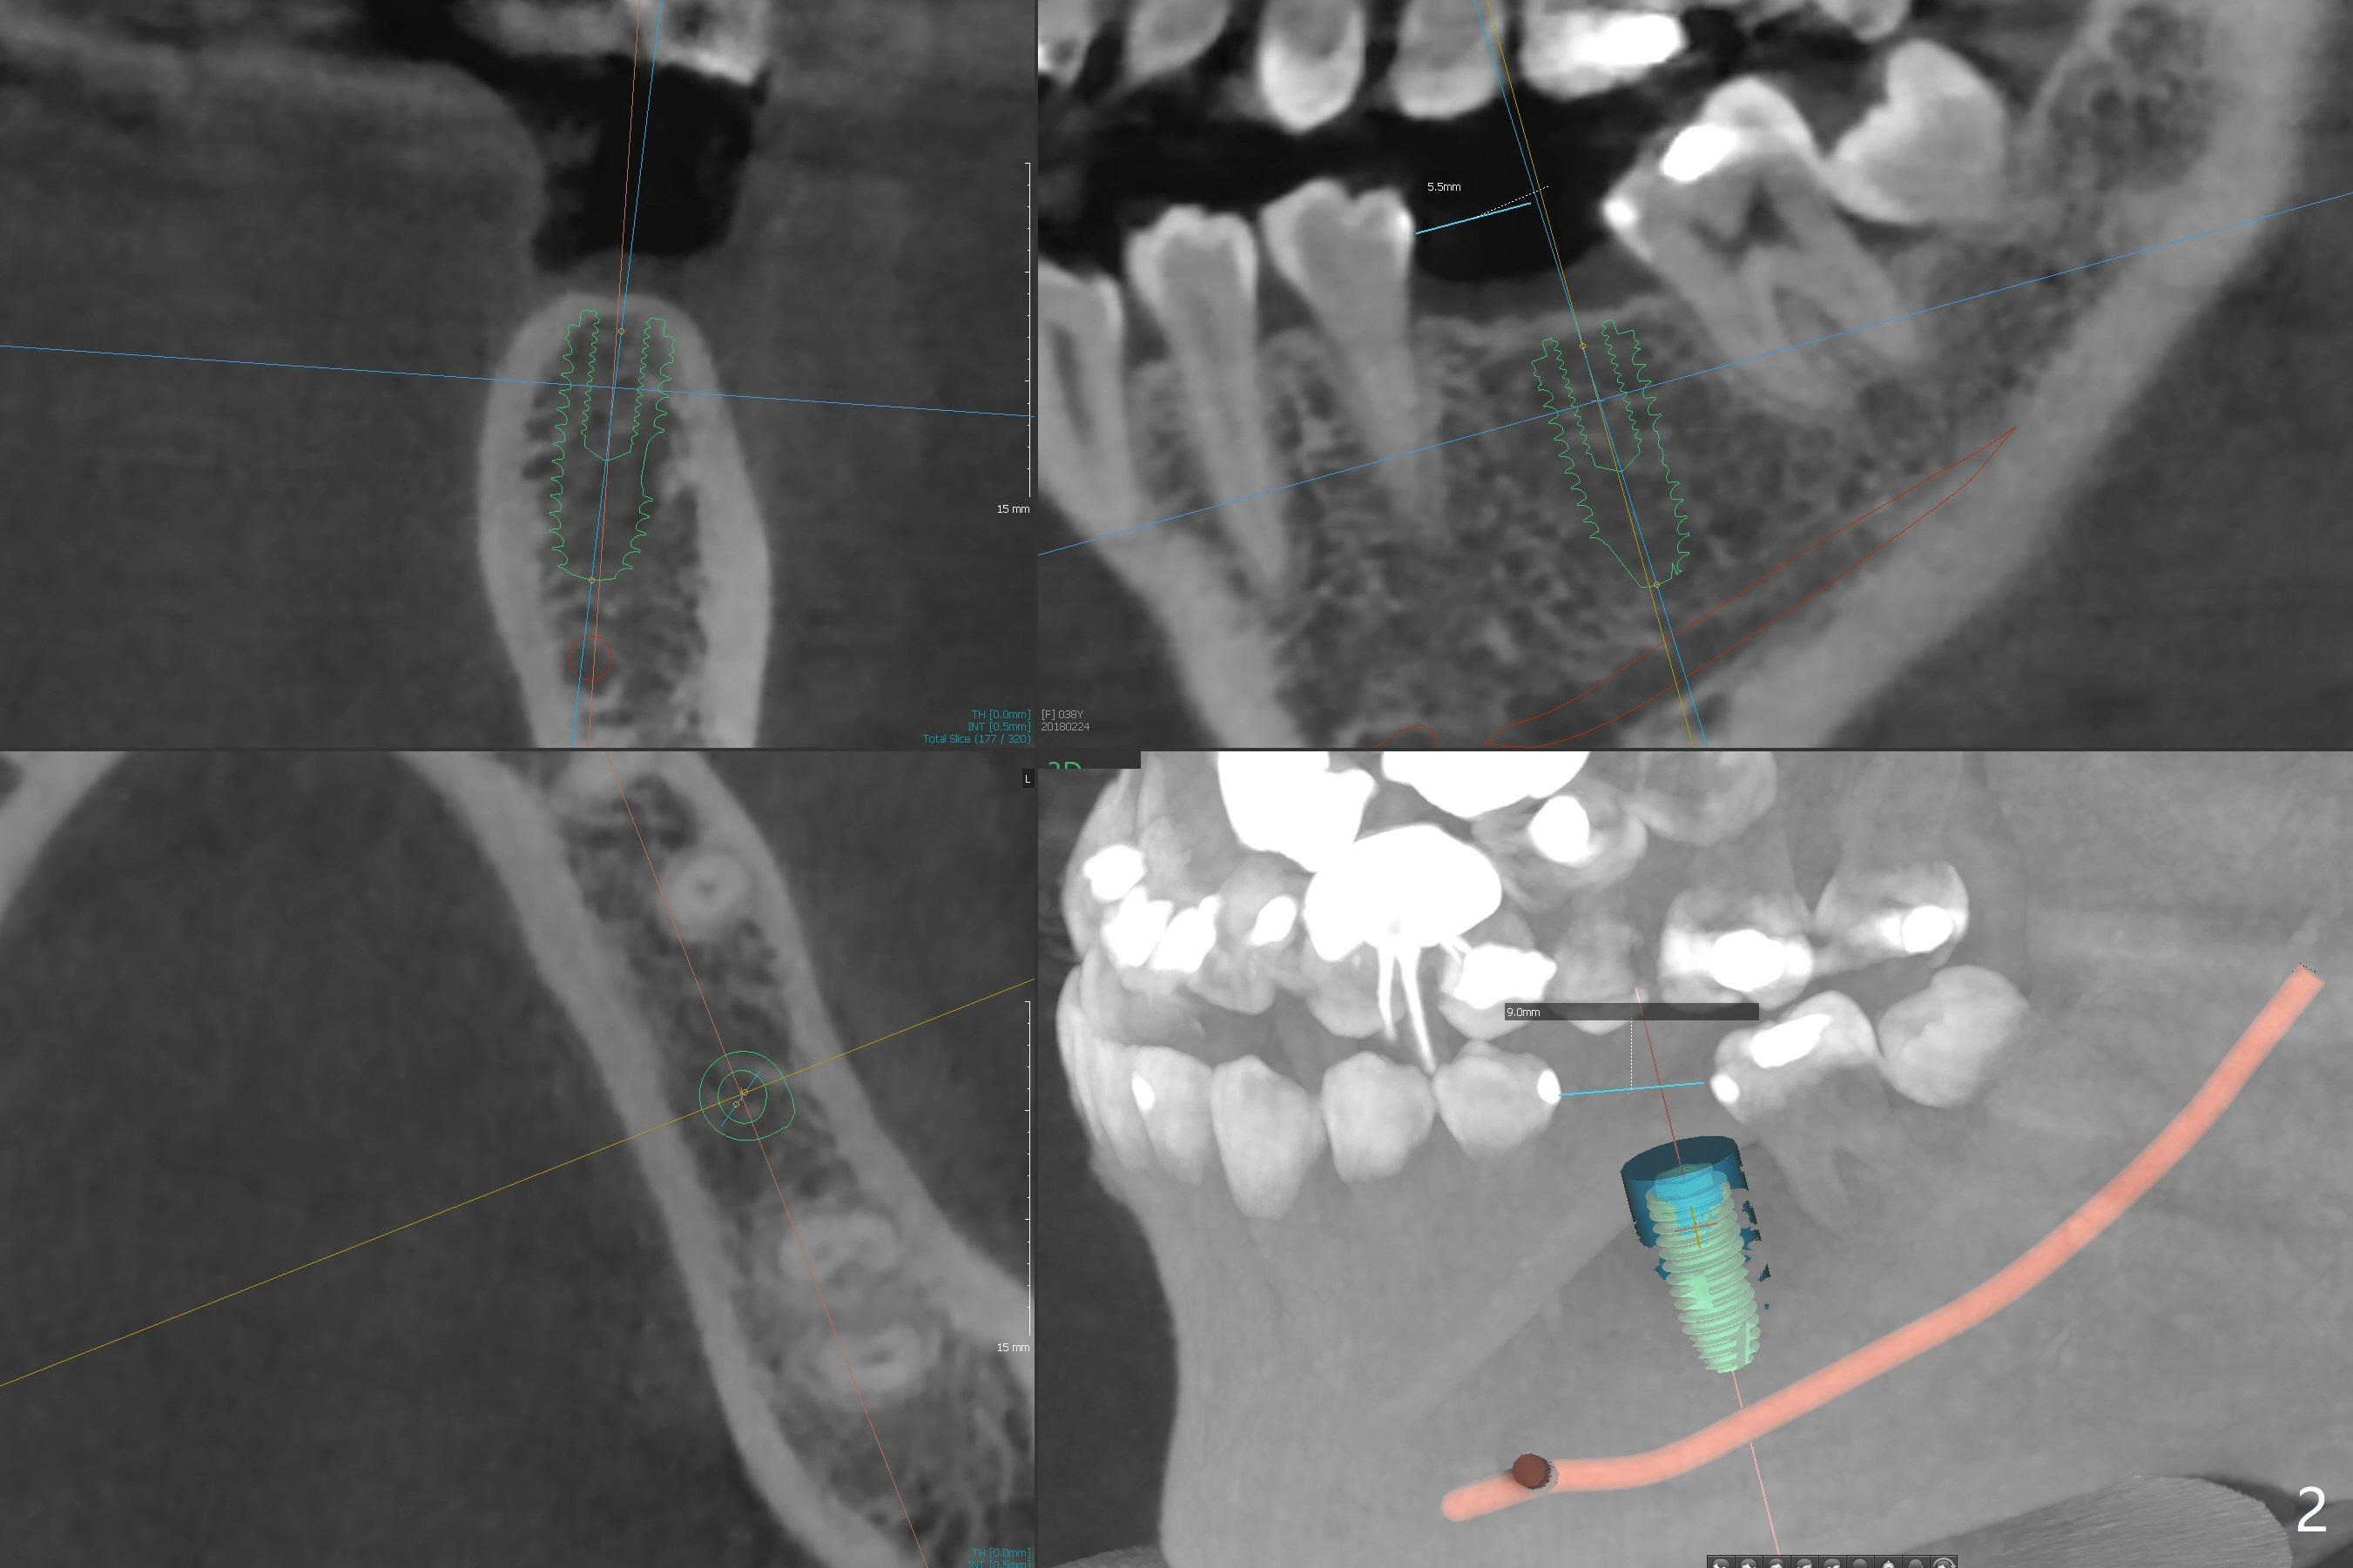

A 38-year-old woman requests implant restoration at #19. The mesiodistal width of the edentulous area is 9 mm (Fig.1) with the tooth #18 mesial shift and inclination. Place an implant (5x11.5 mm) slightly distal (4.5 mm vs. 5.0-5.5 mm in Fig.2) so that the implant will be in the center of the edentulous area after postop orthodontics (uprighting the tooth #18). Also place the implant slightly more lingually (upper left image). Reports from lab are shown in Fig.3-7.